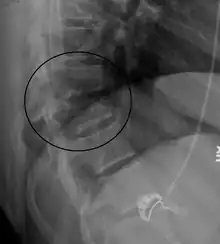

A Chance fracture of T10 and fracture of T9 due to a seatbelt during an MVC.

A flexion-distraction fracture of T10 and fracture of T9 due to a seatbelt during an MVC.

On plain X-ray, a Chance fracture may be suspected if two spinous processes are excessively far apart.[10]